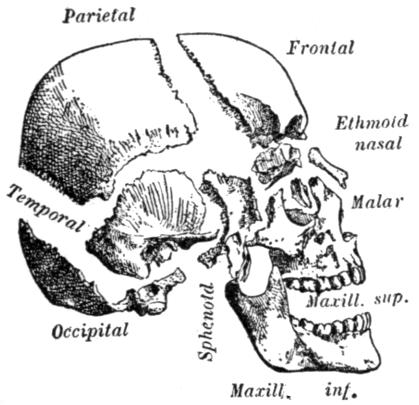

| III. | The Skeleton | H 28 |